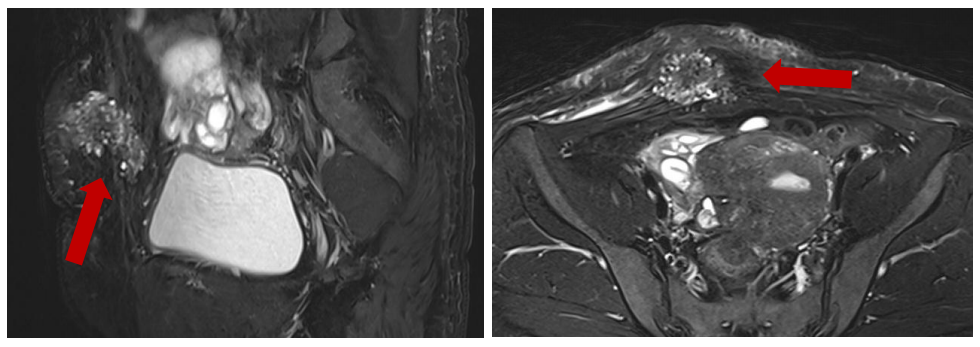

2023年3月我院就诊,体检可扪及剖宫产疤痕处右上方扪及直径约5-6cm肿块,边界不清,轻压痛,表面皮肤未见明显异常;CA125 293IU/mL,AMH 0.72ng/mL,盆腔及腹壁MRI提示:下腹壁下见团块状稍高信号,部分突向盆腔,范围约5.8×4.5×4.1cm,内异症首先考虑;子宫72×60×58mm,肌腺症伴多发肌瘤,大者20×25×21cm;建议GnRHα注射后评估手术方式,患者要求考虑,未进一步复诊;

MRI:右下腹部皮下异常信号3.8×3.9×4.1cm,累及腹直肌,考虑内异症可能;子宫肌腺症合并肌腺瘤,后壁与乙状结肠粘连可能;

超声与MRI:是首选无创手段,可明确病灶位置、范围及深度。典型征象包括腹壁肌层内不均质结节、囊实性包块伴血流信号,需重点评估是否浸润肌层固有层(muscularis propria),对于复杂性腹壁包括,详细描述病灶与肠壁、膀胱、神经的毗邻关系,以优化手术方案,必要时进行多学科讨论。